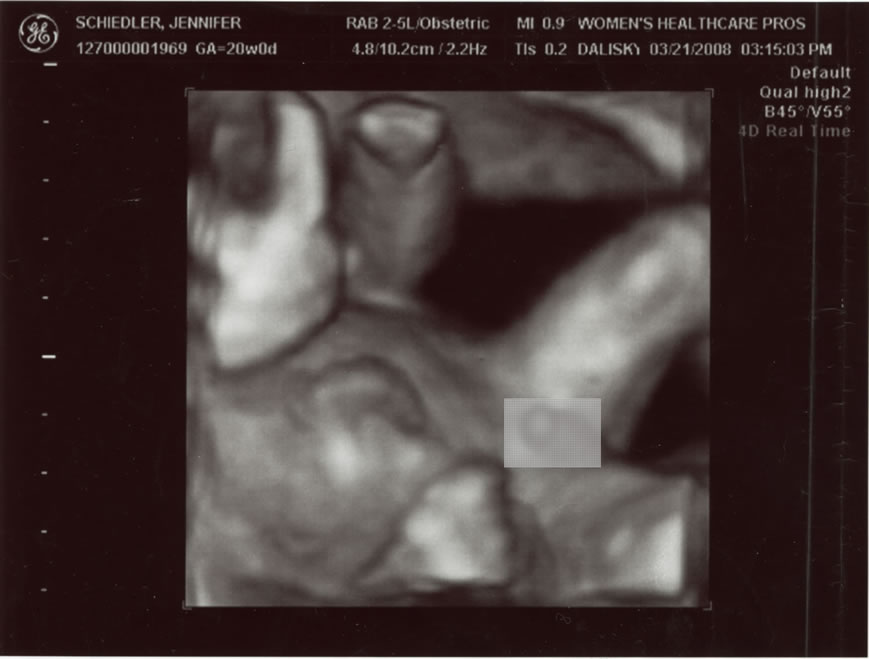

Little Brother showed his parts but never did give us a good shot at his face  1 of 5